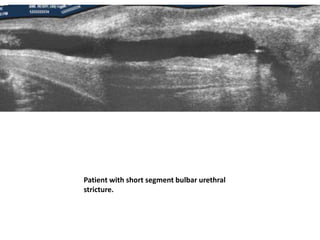

Two ' stomach bubbles' are posterior to

kidney and abutting them. They should be

urinoma.

• Ultrasound • Antenatalultrasound • On antenatal ultrasound the appearance is that of marked distention and hypertrophy of the bladder, hydronephrosis and hydroureter may or may not be present • in severe cases oligohydramnios and renal dysplasia. • keyhole sign may be seen on ultrasound due to the distention of both the bladder and the urethra immediately proximal to the valve • Unfortunately such findings are generally not seen before 26 weeks of gestation, and as such are not frequently identified on routine morphology screening, usually carried out around 18 weeks gestation

• 55.

Typical key-hole appearanceof urinary bladder when seen in long axis.

• 56.

Two ' stomachbubbles' are posterior to kidney and abutting them. They should be urinoma.